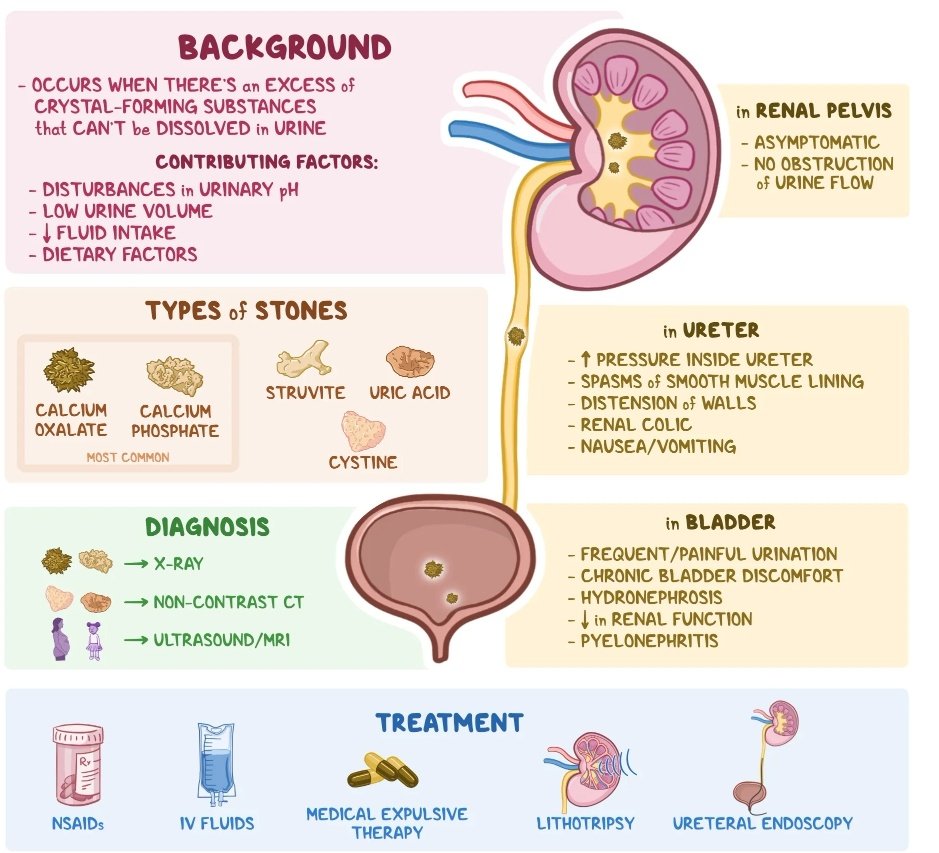

⛔اسباب تكوين الحصوات وليه أحنا من اكثر الدول الي تعاني من الحصوات.

⛔مضاعفات ترك الحصوات وعدم علاجها.

✅طرق الوقاية.

✅طرق العلاج الجراحيه وغير الجراحية.

⛔اسباب تكوين الحصوات وليه أحنا من اكثر الدول الي تعاني من الحصوات.

⛔مضاعفات ترك الحصوات وعدم علاجها.

✅طرق الوقاية.

✅طرق العلاج الجراحيه وغير الجراحية.

❇طرق علاج حصوات الكلى والمسالك البولية..

✅الطرق العلاجيه بالادوية :

1️⃣ادوية تذويب الحصوات تكون لحصوات القابله للذوبان مهما كان حجمها فقد تذوب الحصوات عن طريق زيادة قلوية البول.

2️⃣ادوية توسيع الحالب للحصوات الصغيره تساعد في اندفاعها من الحالب

✅الطرق العلاجيه بالادوية :

1️⃣ادوية تذويب الحصوات تكون لحصوات القابله للذوبان مهما كان حجمها فقد تذوب الحصوات عن طريق زيادة قلوية البول.

2️⃣ادوية توسيع الحالب للحصوات الصغيره تساعد في اندفاعها من الحالب

2️⃣ المناظير والتكسير بالليزر..

تعتبر اكثر الطرق استخداما وهي امنه الى حد ما اذا تم عملها من قبل المختصين و لا تحتاج اي شق جراحي .

تعتبر اكثر الطرق استخداما وهي امنه الى حد ما اذا تم عملها من قبل المختصين و لا تحتاج اي شق جراحي .